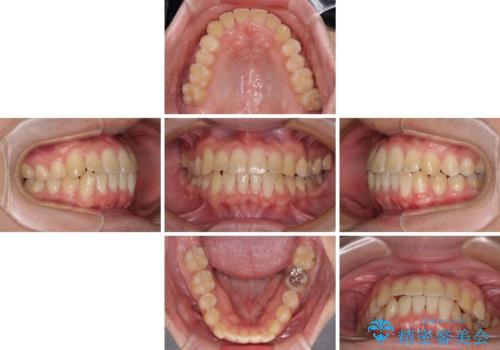

- 前歯のクロスバイトを気にして来院された患者様です。

骨格的には問題がなかったため、インビザラインを用いて咬み合わせを改善していくこととしました。

インビザライン特有の、奥歯の咬み合わせの問題もなく、しっかりと歯列を改善することができました。

舌側転位している上顎側切歯(内側に引っ込んでいる真ん中から2番目の歯)は、インビザラインが最も移動を苦手とする歯であり、これ以上の改善を望まれる場合にはワイヤー矯正、あるいはワイヤー矯正の併用をお勧めいたします。